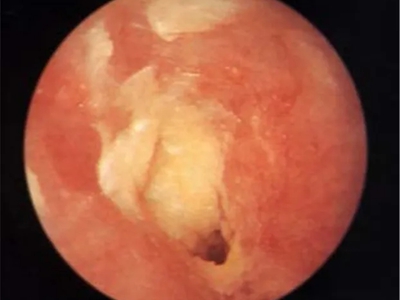

霉菌性外耳道炎耳朵里有黄白色干酪样物质图

霉菌性外耳道炎患者外耳道上有许多白色鳞屑,并且呈簇状分布,相互之间会融合成片,但是边缘破碎,形似海岸线,周围还有散在的鳞屑。